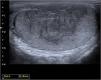

Carcinoma embrionario puro de testículo: presentación de un nuevo caso y revisión de la literatura

Pure embryonal carcinoma of the testis: A new case report and review of the literature